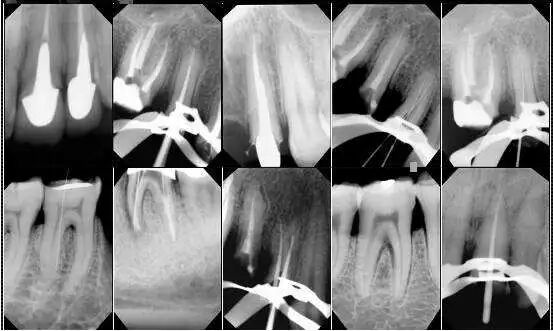

其实口腔摄影,对于我们牙医都是一个挑战的。

为了能拍出最能还原病情的照片,需要单反相机,微距镜头,环形闪光灯等外,还需要开口器、反光镜以及背景板等专业辅助器材用品,还得各种看书。

所以这样随手一拍的照片,恐怕是瞧不出什么来,更何况牙医看病不仅仅是望诊,还有探诊,扪诊等。